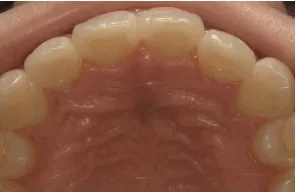

- 症例1

治療期間 約8カ月

治療費 23.1万円(税込)